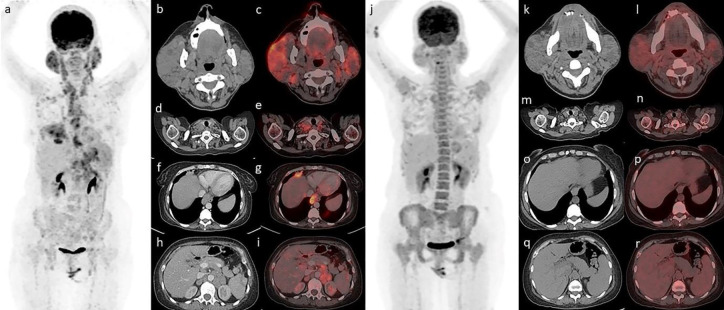

Primary Sjögren syndrome (SS) is an autoimmune disease affecting exocrine glands, with predisposition to development of lymphoma (lymphomagenesis). We report a case of Sjogren's syndrome and discuss the role of FDG PET/CT in the primary diagnosis of lymphoma transformation in SS. Furthermore, we reviewed the literature regarding the utility of FDG PET/CT to assess systemic disease activity and also its role in the SS associated lymphoma with light into the new PET tracers that can be explored for these indications in the future. Published data suggest promising role of FDG PET/CT in SS associated lymphomas, and demands larger studies for its establishment.